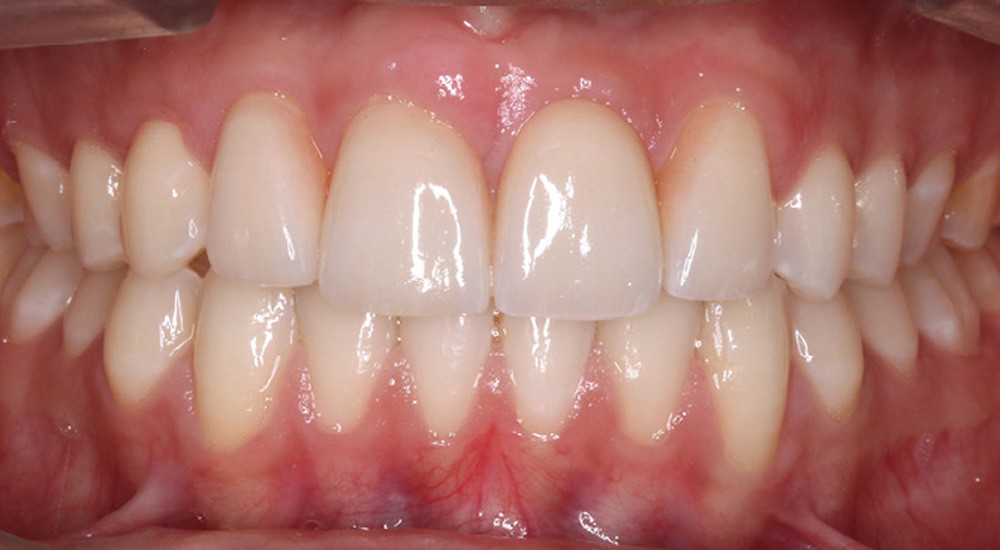

Le débaguage est réalisé au bout de 22 mois. Pour harmoniser la position des collets et redonner une hauteur coronaire acceptable aux nouvelles incisives centrales, une gingivectomie est effectuée, en accord avec le dentiste en charge des réalisations prothétiques. La croissance alvéolaire n’étant pas terminée, le rendu parodontal et esthétique évoluera. Ceci impose de différer la réalisation prothétique d’usage pour avoir un résultat stable dans le temps. Il est donc convenu de reprendre le traitement juste avant de réaliser les étapes prothétiques. Le traitement orthodontique comportant deux phases, les objectifs de finitions de la première phase sont abaissés pour réduire la durée globale de traitement.

Plusieurs difficultés ont été rencontrées durant le traitement. L’impact psychologique des extractions d’incisives centrales a été lourd pour le patient, dont la promesse d’un sourire harmonisé a permis de surmonter cette épreuve. Ensuite, la gestion de la transposition était délicate. Il a fallu également accepter un rendu esthétique perfectible jusqu’à la fin de la croissance. La gestion de la dysharmonie dento-parodontale au niveau des incisives latérales et des canines était essentielle ; une correction parodontale et orthodontique, en jouant sur les informations de deuxième et troisième ordres, a permis une transition esthétique optimisée. L’outil de prévisualisation Digital Smile Design s’est en ce sens avéré très utile pour définir les impératifs propres à la prothèse (fig. 4a,b). Des frais pour la parodontie et la prothèse se sont enfin ajoutés aux dépenses orthodontiques (deux phases de traitement). Le rendu esthétique est satisfaisant en fin de traitement, avec une harmonisation du sourire et du profil (fig. 5 et 6). Les extractions n’ont pas appauvri le sourire. La qualité des réalisations prothétiques, l’environnement parodontal remanié et l’occlusion de fin de traitement font espérer un bon devenir dans le temps.